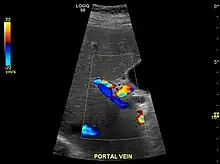

Caudate lobe hypertrophy on ultrasound due to cirrhosis

Hepatofugal (non-forward) flow in portal vein

Imaging

Ultrasound is routinely used in the evaluation of cirrhosis.[34] It may show a small and shrunken liver in advanced disease. On ultrasound, there is increased echogenicity with irregular appearing areas.[51] Other suggestive findings are an enlarged caudate lobe, widening of the fissures and enlargement of the spleen.[52] An enlarged spleen, which normally measures less than 11–12 cm (4.3–4.7 in) in adults, may suggest underlying portal hypertension.[53] Ultrasound may also screen for hepatocellular carcinoma and portal hypertension.[34] This is done by assessing flow in the hepatic vein.[54] An increased portal vein pulsatility may be seen. However, this may be a sign of elevated right atrial pressure.[55] Portal vein pulsatility are usually measured by a pulsatility indices (PI).[54] A number above a certain values indicates cirrhosis (see table below).